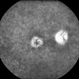

- Behcet's Disease, Behcet's uveitis, FA late phase leakage

- DEEPAK BHOJWANI, RAGHUDEEP EYE HOSPITAL, AHMEDABAD.

- A 19-year-old boy presented with with recurrent oral and genital ulcers along with blurring of vision. Systemically he was HLA B-51 Positive suggesting Behcet's Disease. The FFA photograph depicts the classic small vessel immune mediated vasculitis predominantly affecting the capillaries (capillaropathy).